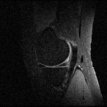

Table 1 shows the performance of both approaches on the test data, in addition to the error lower-bounds obtained by the best -sample approximations with respect to the Fourier basis. It appears that the learning based approach slightly outperforms the randomized variable density based approach.

However, the slight numerical improvements are actually accentuated when we look at the details of reconstructions, shown in Figure 2 for the test Patient #13. It is clear that the learning-based reconstructions provide more details especially for and .